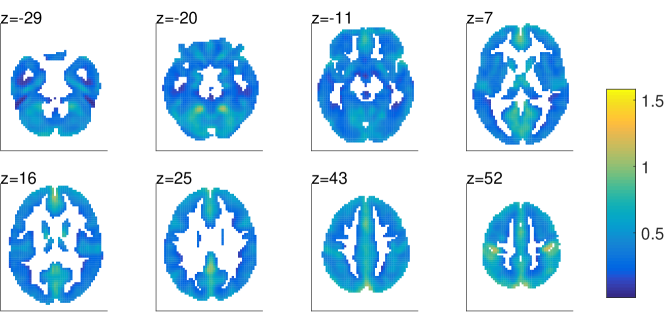

The expectation of the log precision of the noise 𝝉𝝉\bm{\tau}, averaged over subjects, is shown in Fig. 4(a). As the estimated precision varies over voxels, this hints that the assumption of heteroscedastic noise is supported by the data. Furthermore, the regions of high precision are related to the experimental design, where a high signal to noise ratio is expected. The noise precision estimates by pFA are similar those of psFA and are therefore not shown.

(a) Motor experiment: Regions showing high noise precision are related to the experimental design, i.e. motor cortex and visual area.

Refer to caption

(b) Resting state (psFA): Regions with high noise precision are mostly located around the DMN.

Figure 4: The expectation of log precision (log(𝝉(b)\,\left\langle\,\log(\bm{\tau}^{(b)}\,\right\rangle\,), averaged over subjects/sessions.